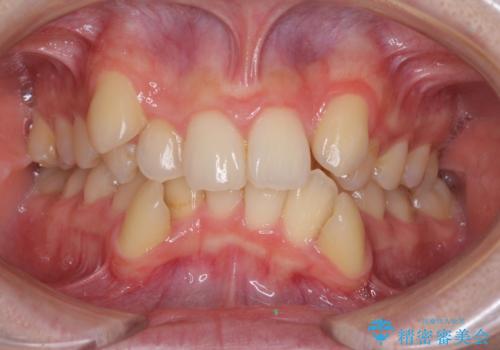

前歯のデコボコを治したい 費用を抑えた抜歯矯正